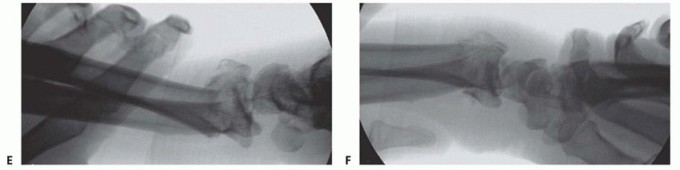

TECH FIG 2 •(continued)D. The ECRL and ECRB tendons just proximal to the abductor pollicis longus in the forearm. E. Development of the interval between the ECRL and ECRB tendons to gain access to the radius shaft. F. The proximal aspect of the plate over the radius and in between the ECRL and ECRB. It is important to ensure that the plate runs within the second compartment and not superficial to the first and third compartment tendons. G. The plate is advanced proximal to distal and emerges distally over the second metacarpal. H. A third incision is marked out just ulnar to the tubercle of Lister. I. The extensor pollicis longus tendon has been released from its compartment, and bone graft is inserted through the dorsal fracture line just ulnar to the bridge plate.